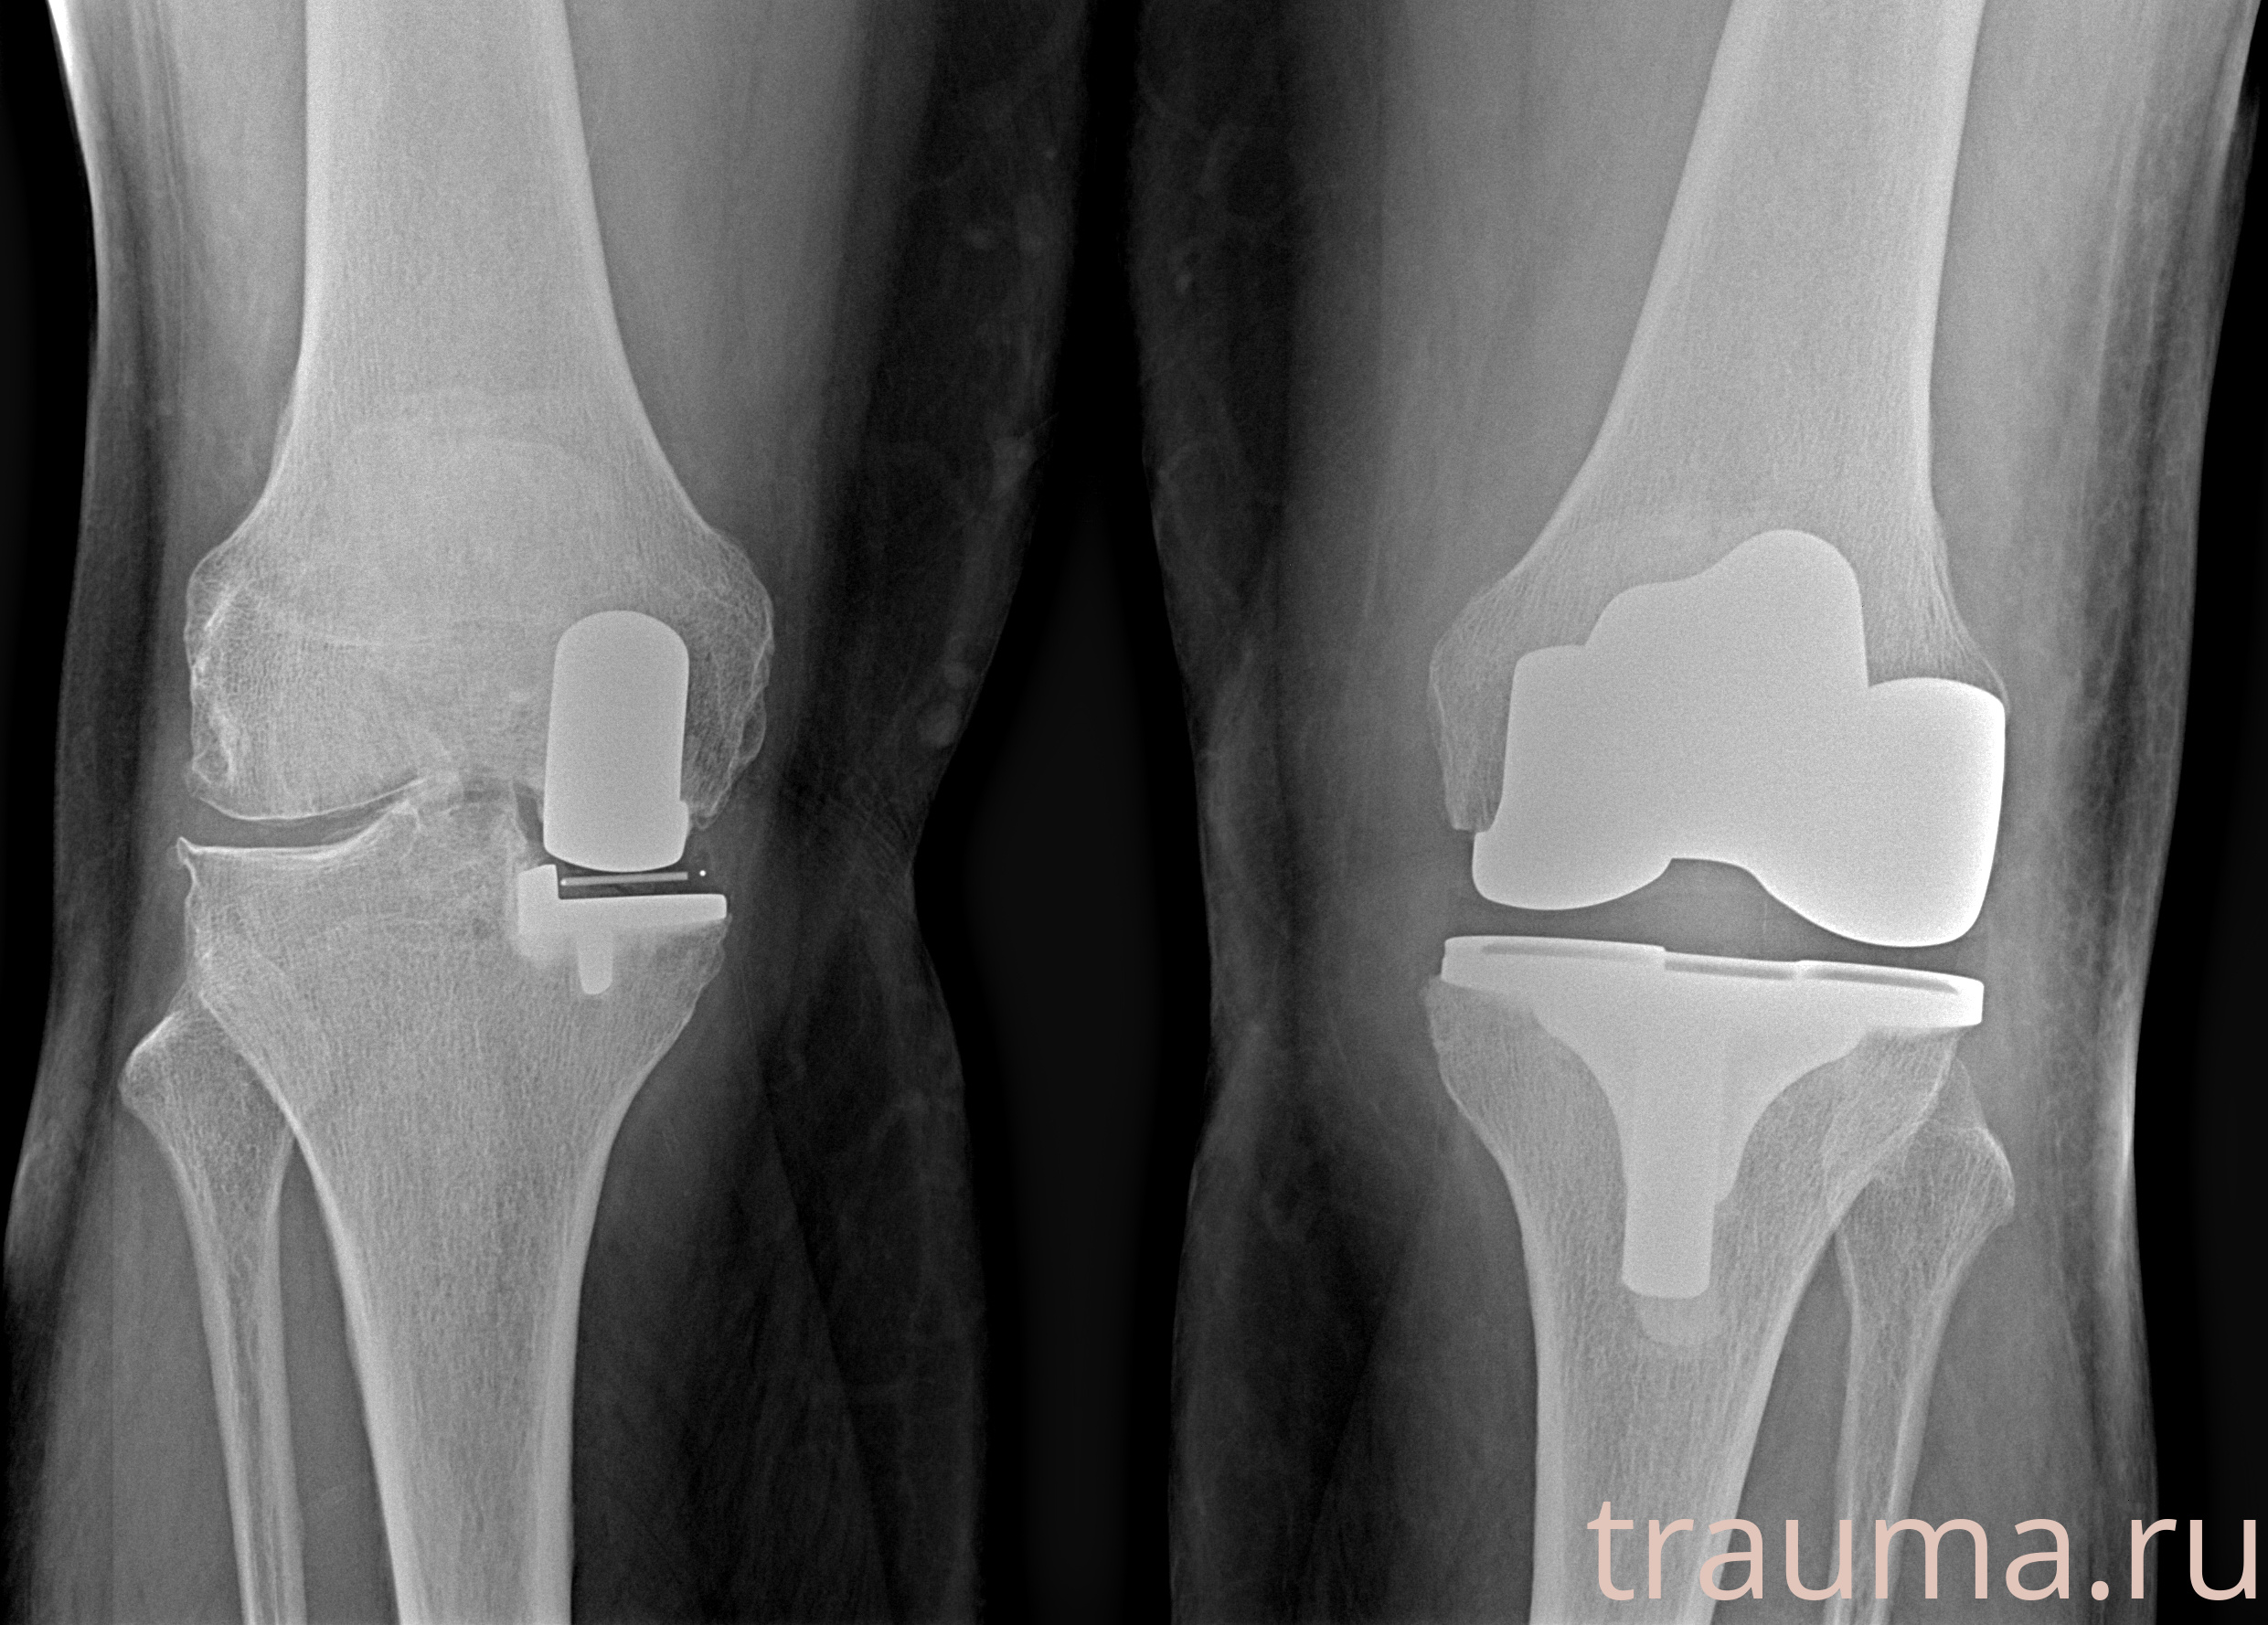

Правый

Рентгенограммы